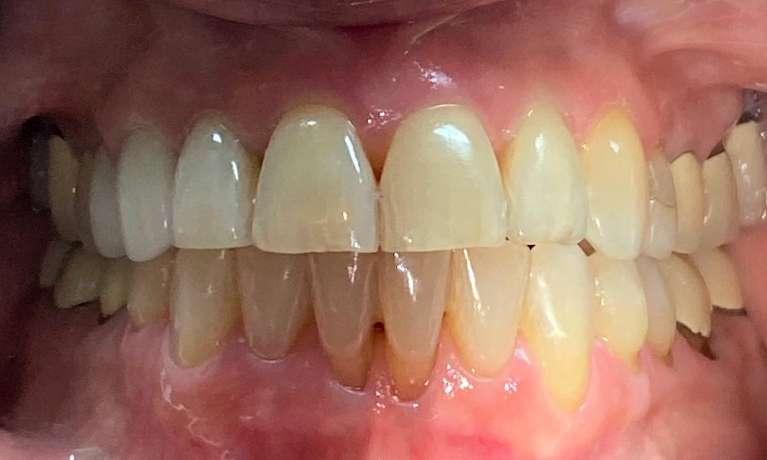

This patient had worn down her teeth over the years due to a bad bite. Dr. Farahani used Invisalign to move the teeth into a position where they could be restored and then placed 4 crowns top and bottom to give her back the length of her front teeth. This is a great example of the conservative restorative care provided at Harmony Dental Wellness to bring your mouth and body back into balance!